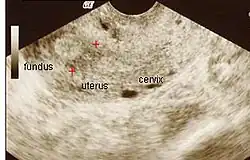

Amniotic sheet on ultrasound